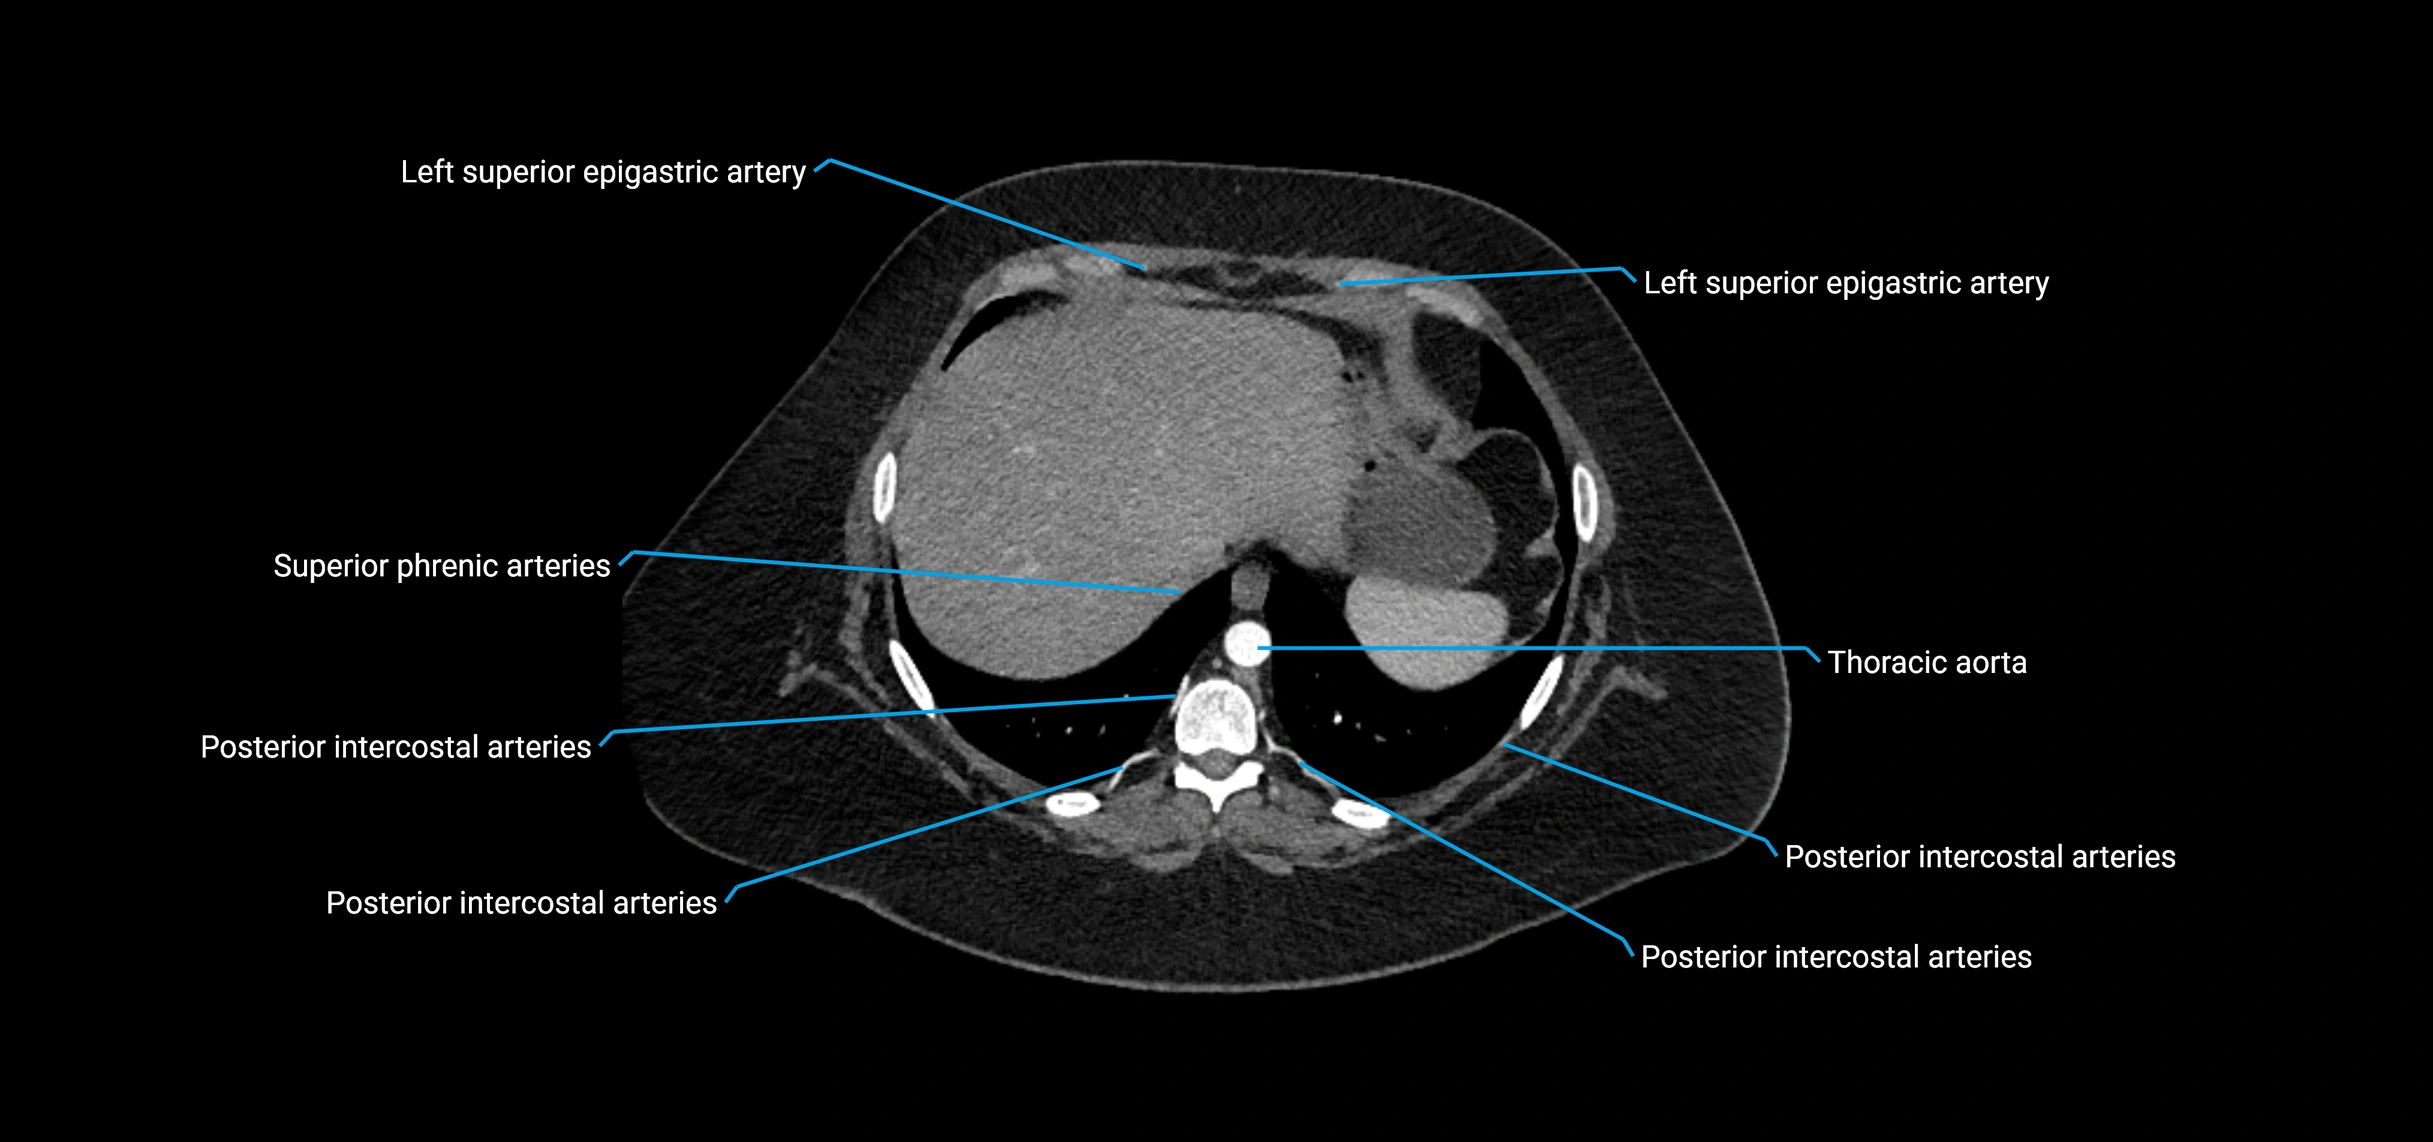

MRI images

image

MRI Appearance

T1-weighted images:

• Flowing blood appears as a signal void (black lumen)

• Vessel wall appears as a thin hypointense rim; retroperitoneal fat enhances contrast

T2-weighted images:

• Lumen remains a signal void due to flow

• Adjacent edema, hematoma, or aneurysm wall thrombus may appear hyperintense

MRA (Magnetic Resonance Angiography):

• Contrast-enhanced MRA provides high-resolution imaging of the aorta and its branches

• Allows 3D reconstruction of visceral, parietal, and terminal branches

• Excellent for evaluating aneurysm size, dissection flap, stenosis, or preoperative planning

• Non-invasive alternative to conventional angiography